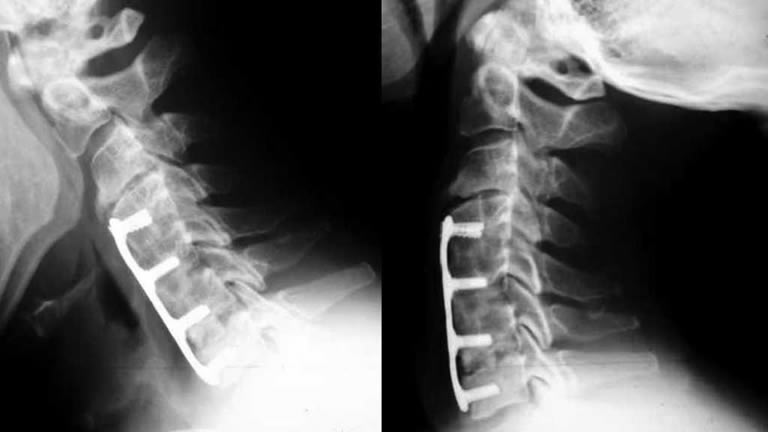

Los paquetes de Turismo Médico del Hospital Puebla ofrece para Disectomía y Artrodesis Cervical, donde se tratan las vértebras dañadas o desgastadas en el cuello. En este procedimiento, un cirujano quita la vértebra dañada, aliviando la presión sobre los nervios pinzados, y llena el espacio vacío de la vértebra con hueso. Se puede realizar de uno o dos niveles.